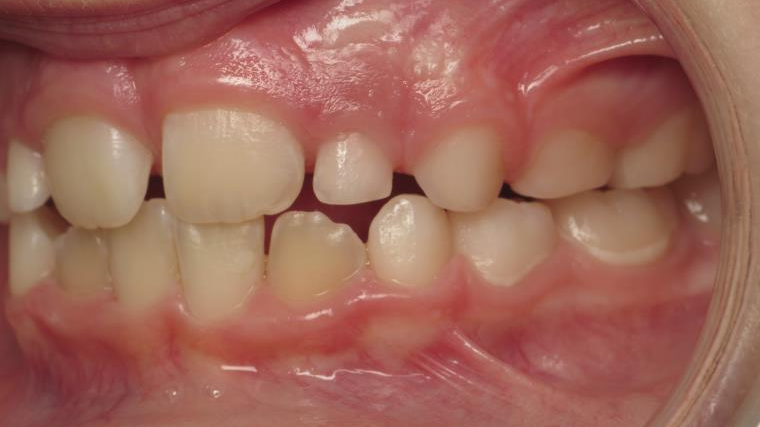

Décalage entre les dents d avant en arrière

appareillage mobile

surveillance évolution de la dentition pendant 4 ans